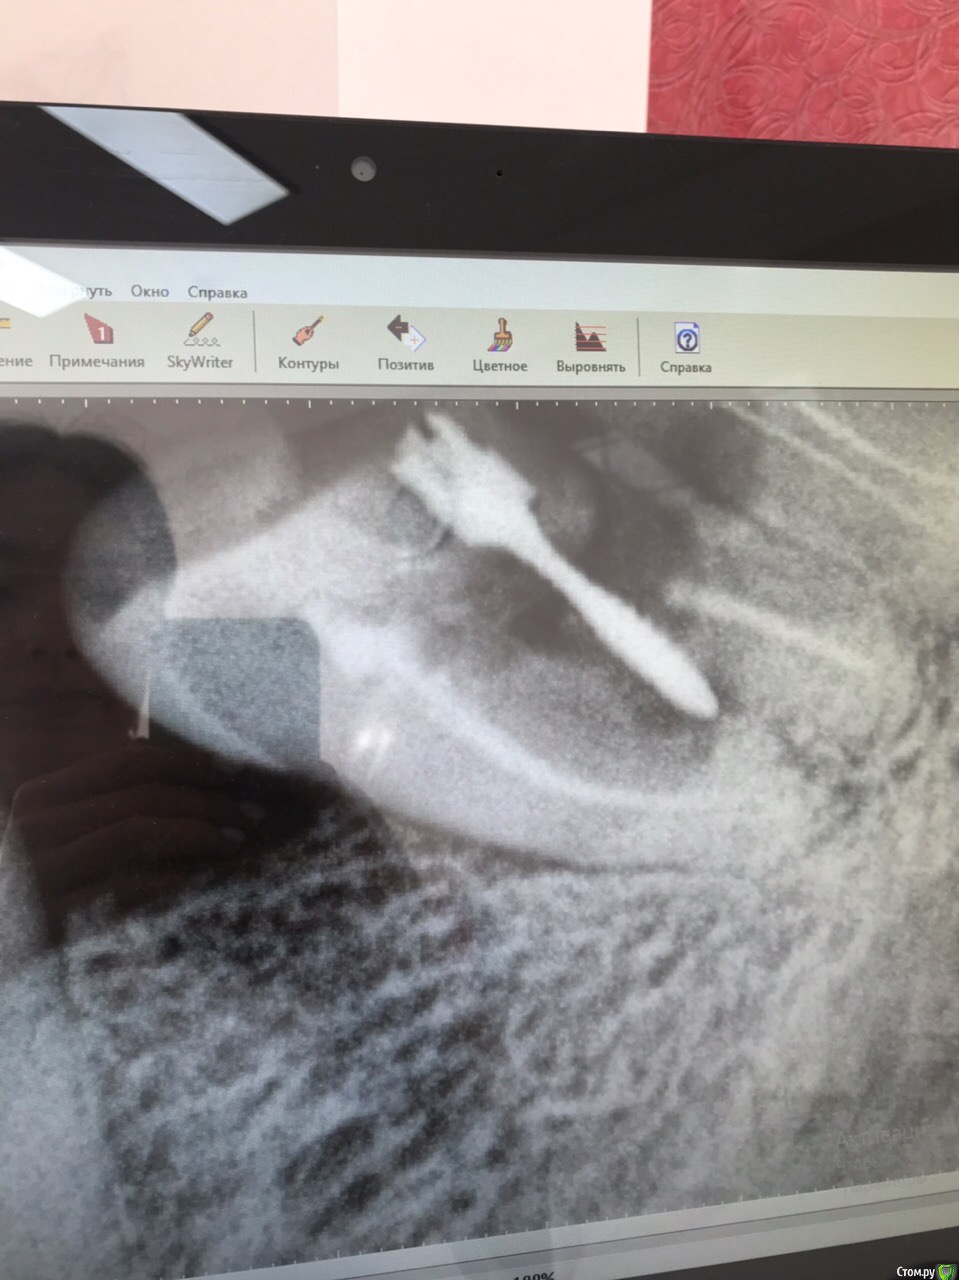

FVValerievna Опубликовано 14 сентября, 2019 Поделиться Опубликовано 14 сентября, 2019 Здравствуйте, подскажите пожалуйста, возможно ли, что пропущен канал? Ситуация такая: в полости рта четко видно 4 устья, на рентгене с инструментами тоже видно 4 канала, но на контрольном снимке не вижу 4й канал, хотя в полости рта запломбировано все 4 устья. Возможно ли такое наслоение? 1 Ссылка на комментарий

vse32 Опубликовано 14 сентября, 2019 Поделиться Опубликовано 14 сентября, 2019 Наслоение конечно возможно. Но на Вашем снимке после пломбировки видно, что каналов 4 штуки. Ссылка на комментарий